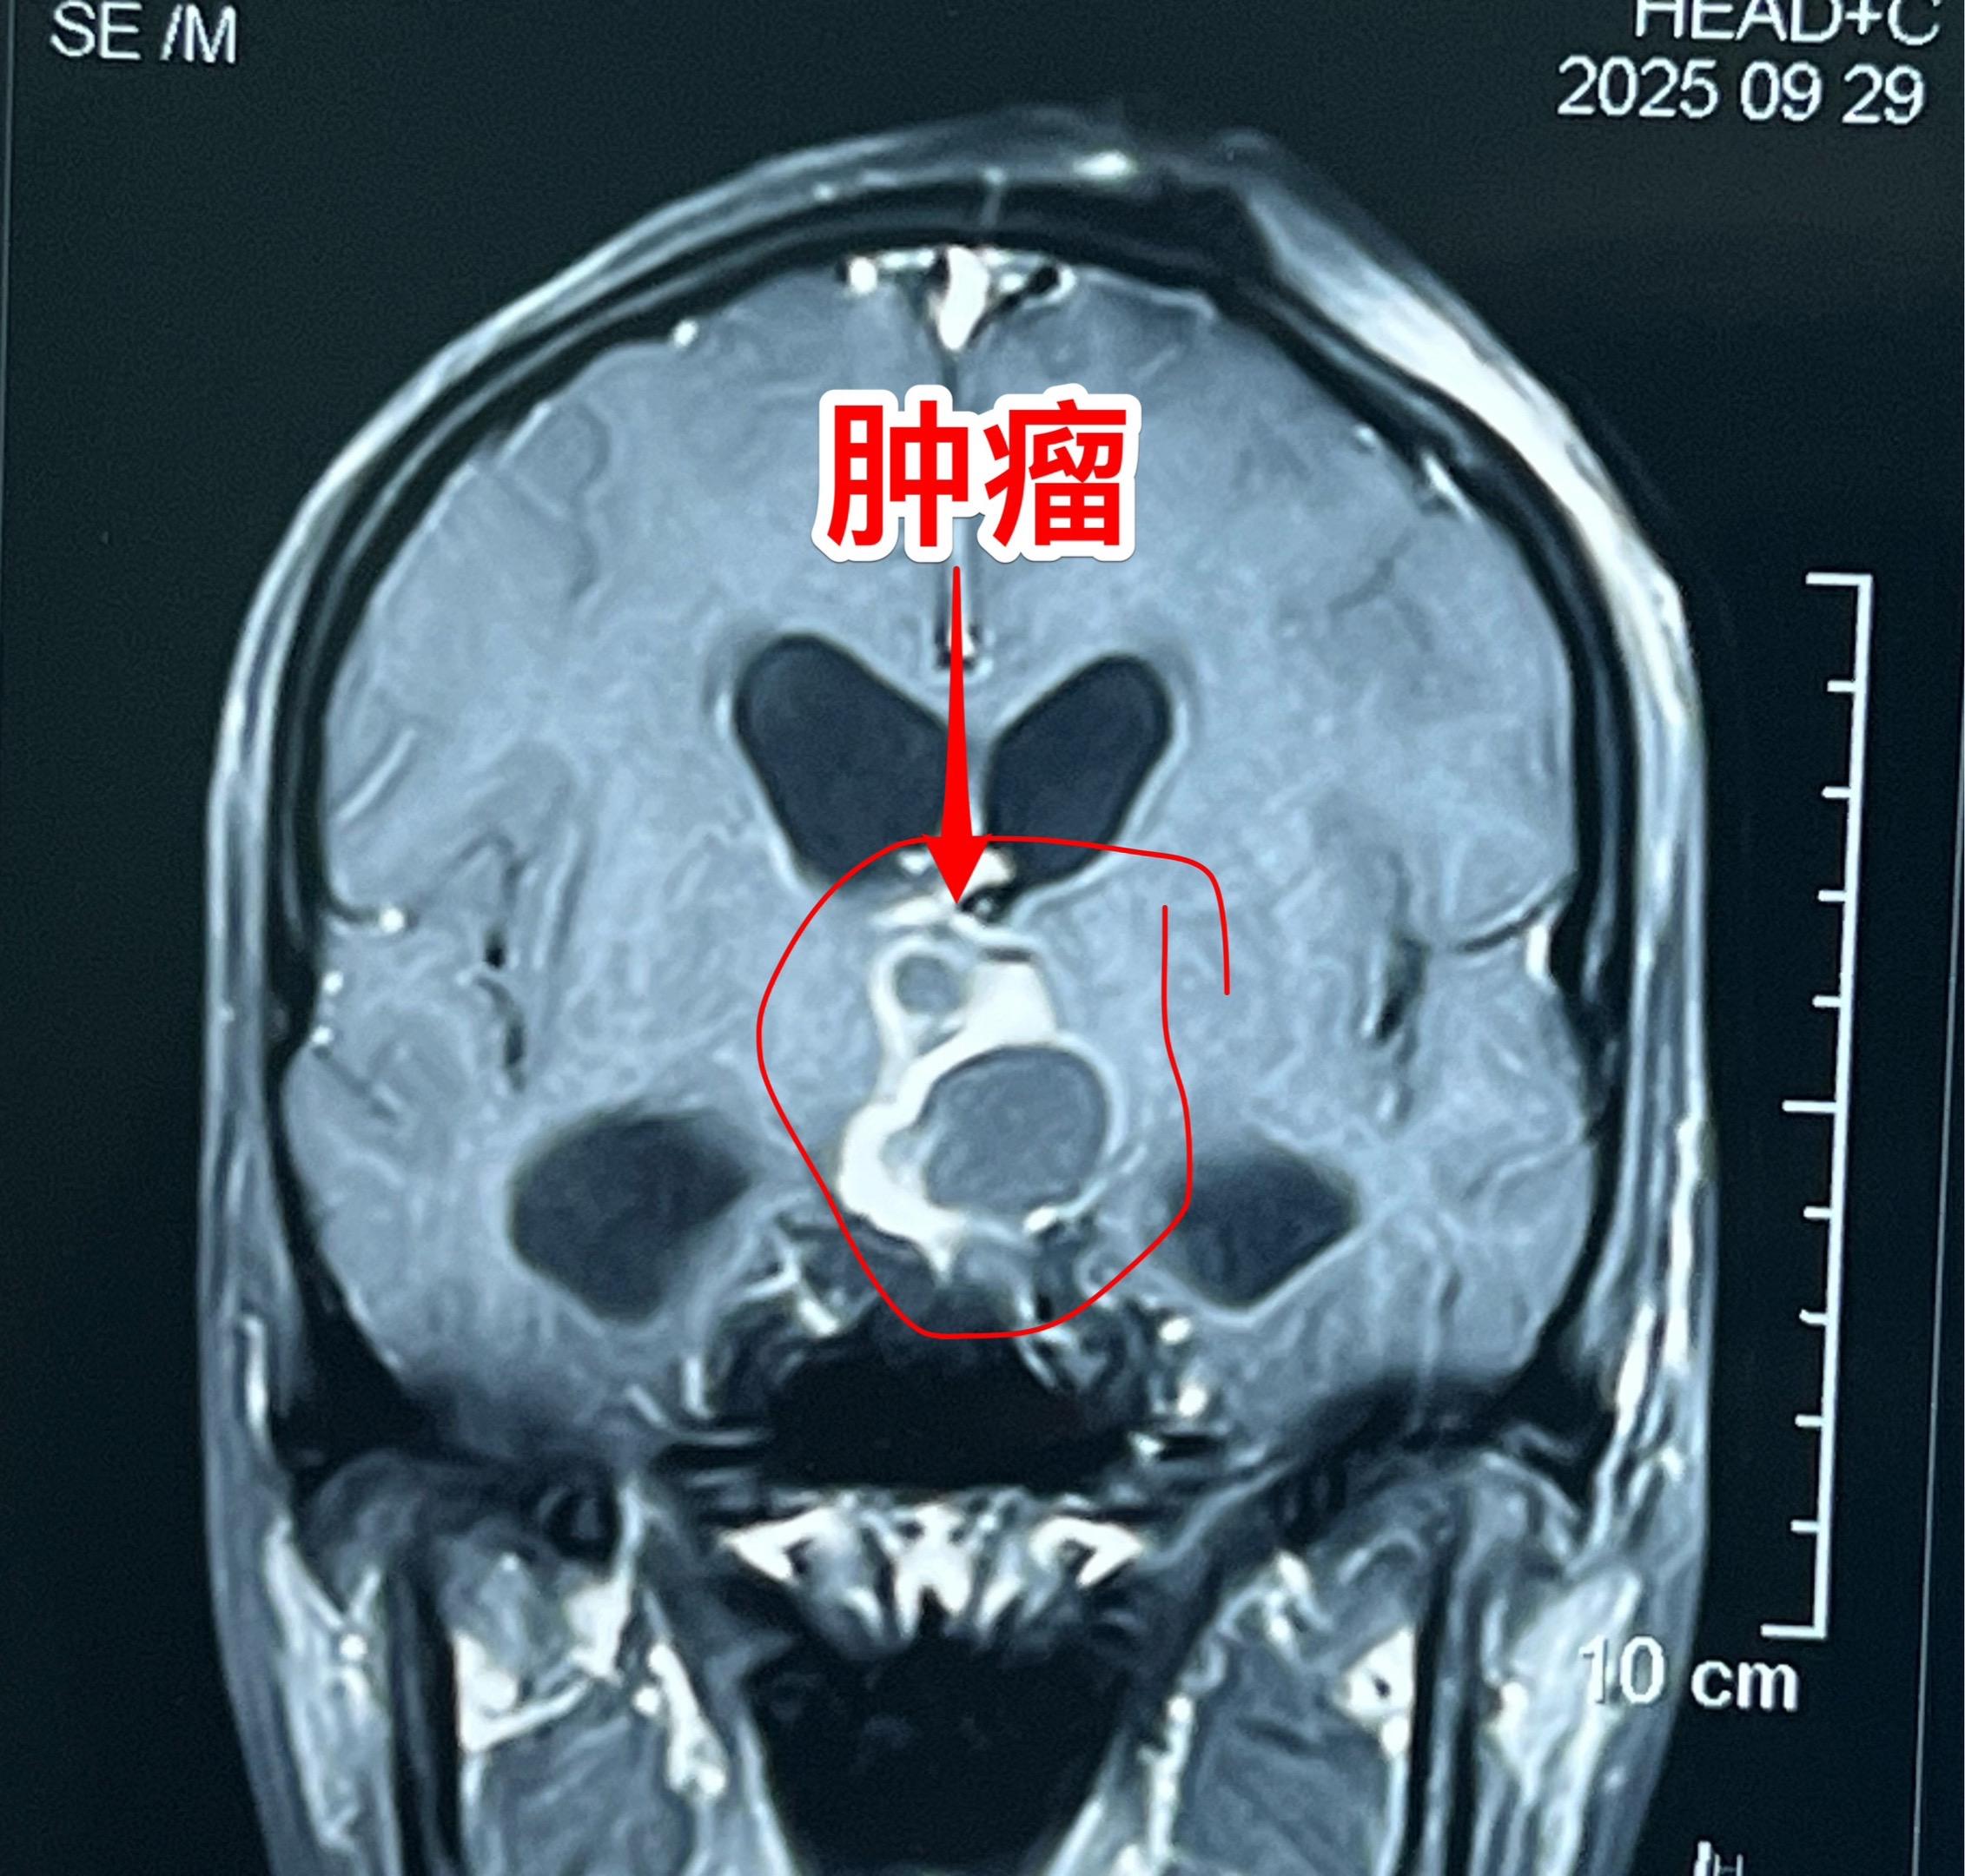

20岁女大学生生病三年身体虚弱如林黛玉。洛阳市女学生,三年前开始出现食欲下降,伴体重减轻。一年前出现多饮多尿症状、内分泌紊乱。怀疑是糖尿病,未得到有效治疗,症状越来越严重。2025.9病人出现头痛、呕吐、嗜睡。在洛阳市某医院就诊,行磁共振检查发现鞍区肿瘤伴有脑积水。于9月23日行脑室引流术,手术后病人头痛、呕吐症状好转。 9月28日到我院住院。住院时病人精神状态很差,体重才80斤,消瘦、面色苍白,看起来如林黛玉一样弱不禁风。(发病前体重一百多斤。) 9月30日作了开颅手术,切